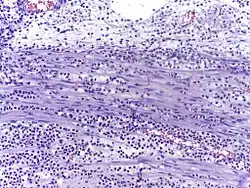

![]() | Fibroblasts | Fibroblasts in intestinal pneumonia | Category: Fibroblasts | Fibroblast |